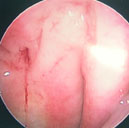

蔡先生因在左頸有腫塊而到耳鼻喉科門診就診(圖5),頭頸部的局部檢查除了左頸有界限糢糊不清的腫塊外其它包括鼻咽部(圖6)並沒有明顯異常,以頭頸部超音波檢查發現淋巴結預測值高於7分(圖7),超音波導引下細針穿刺細胞學檢查懷疑是轉移性鼻咽癌後,接受內視鏡鼻咽部切片證實為鼻咽癌。由於蔡先生超音波導引下細針穿刺細胞學檢查,避免了過去常見的頸部腫塊的切片手術。蔡先生接受放射腺治療後,腫塊即消失,因此可見頸部腫塊的切片手術對於鼻咽癌的診斷治療是不必要的。

圖6. 蔡先生頭頸部局部檢查鼻咽部沒明顯的腫瘤